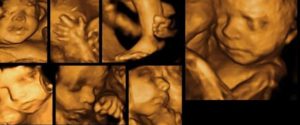

При современном уровне ультразвуковой диагностики на экспертных аппаратах с высоким разрешением квалифицированный врач может с большой долей вероятности определить пол ребенка начиная с 12 недели беременности.

По данным результатов различных изучений в разных клиниках мира, точность диагностики пола будущего ребенка в 11 недель гестации при трансвагинальном УЗИ варьирует от 45% до 92%, в 12 недель – 54-100%, в 13 недель – 56-100%.

Проще говоря, на этом сроке пол ребенка чаще всего можно установить с вероятностью 50:50. Более точно это можно сделать, начиная с 14-16 недели беременности, когда наружные половы органы уже отчетливо становятся видны на экране.

Трехмерная реконструкция гениталий плода мужского (А) и женского (Б) пола

Во вторую половину беременности, когда плод достигает достаточно больших размеров, установление пола не вызывает уже обычно сложностей для врача УЗИ. Мужской пол выставляется при четком определении пениса и мошонки, а женский – при выявлении половых губ.

Пол плода в сроке 12-14 недель беременности, как правило, можно оценить на основании величины угла между половым бугорочком и горизонтальной линией, проходящей вдоль спинки плода.

Если угол между этими структурами больше 30 градусов, то имеется высокий шанс развития ребенка мужского пола. Если же угол меньше 30 градусов или равен нулю, то скорее всего развивается девочка.

Достоверность определения пола ребенка по такой методике при ее четком выполнении достигает 98,0% в 12 недель беременности.

Определение пола по величине угла. Сверху – девочка, снизу – мальчик

У мальчиков видны пенис и мошонка, у девочек большие половые губы. Иногда увеличенный клитор может имитировать половой член.

Улучшает точность диагностики использование УЗИ с трехмерной реконструкцией (3D-УЗИ), которое позволяет более точно рассмотреть гениталии ребенка.

3D-УЗИ позволяет получить объёмную картинку , на которой точно можно увидеть личико малыша и рассмотреть подробности его внешнего вида, узнать пол ребёнка и пересчитать крошечные пальчики.

Отличие 3D-исследования от традиционной процедуры в том, что проводить его можно только в определённые сроки – с 20 по 33 неделю и делается оно только по желанию родителей, так как с медицинской точки зрения ничем не отличается от обычного УЗИ, а стоит дороже в несколько раз.

4D отличается от 3D только возможностью увидеть, как живет ребёнок в матке в режиме реального времени. Трёхмерное УЗИ показывает только статичные кадры, а вот четырёхмерное, благодаря повороту картинки, позволяет увидеть движения малыша и его мимику.